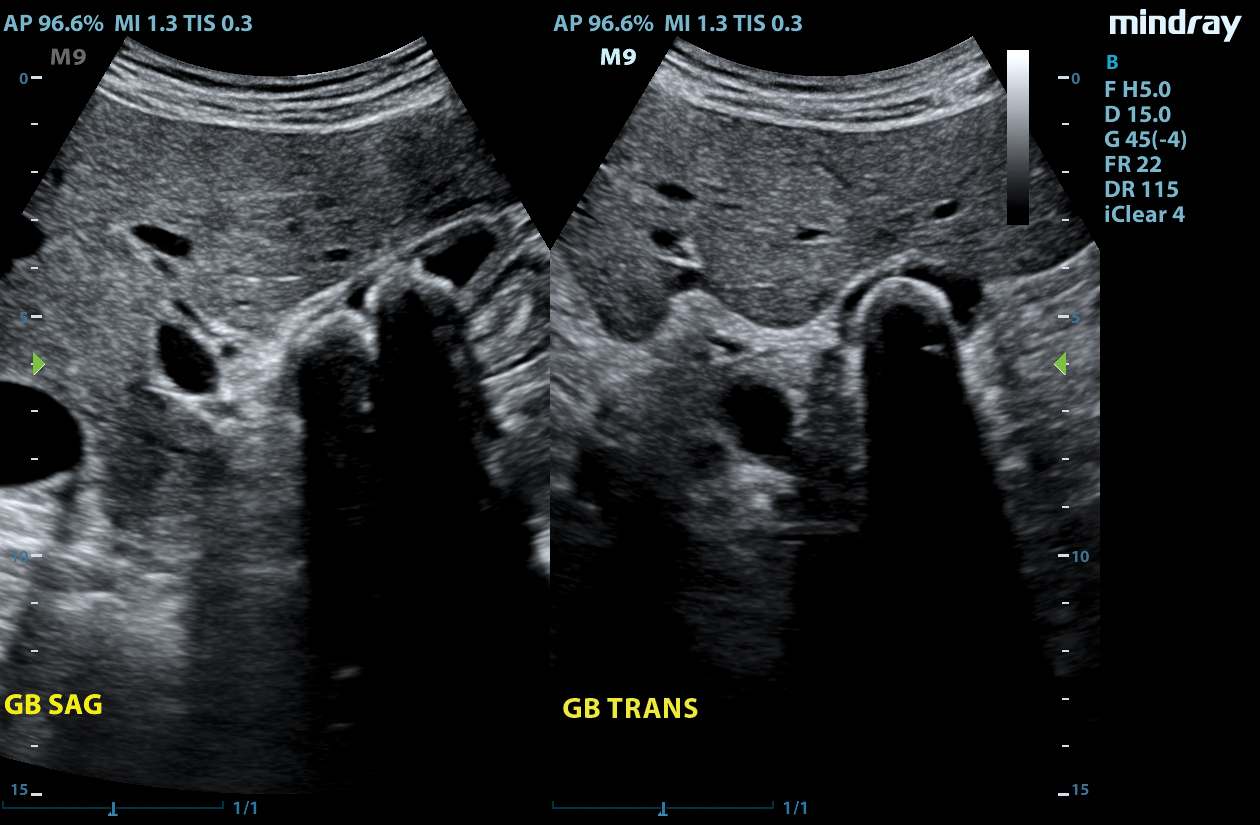

The M9 Ultrasound System Ruby Edition offers a fully-featured, compact ultrasound solution for your most challenging point-of-care exams. Delivering image clarity and advanced capabilities previously only available on larger, cart-based systems, the M9 System defines the new standard for intelligent performance in a mobile, laptop design.

Equipped with single crystal transducers and 3T™ technology for a wide range of exams, the M9 System is a versatile platform for advanced imaging in the vascular lab, emergency departments, critical care environments, and anesthesia practices. The System’s slim profile and ergonomic design allow for effortless flexibility and mobility. Whether it be ultrasound guided procedures at the patient’s bedside or transesophageal echocardiography (TEE) imaging in the critical care unit, this platform can do it all.